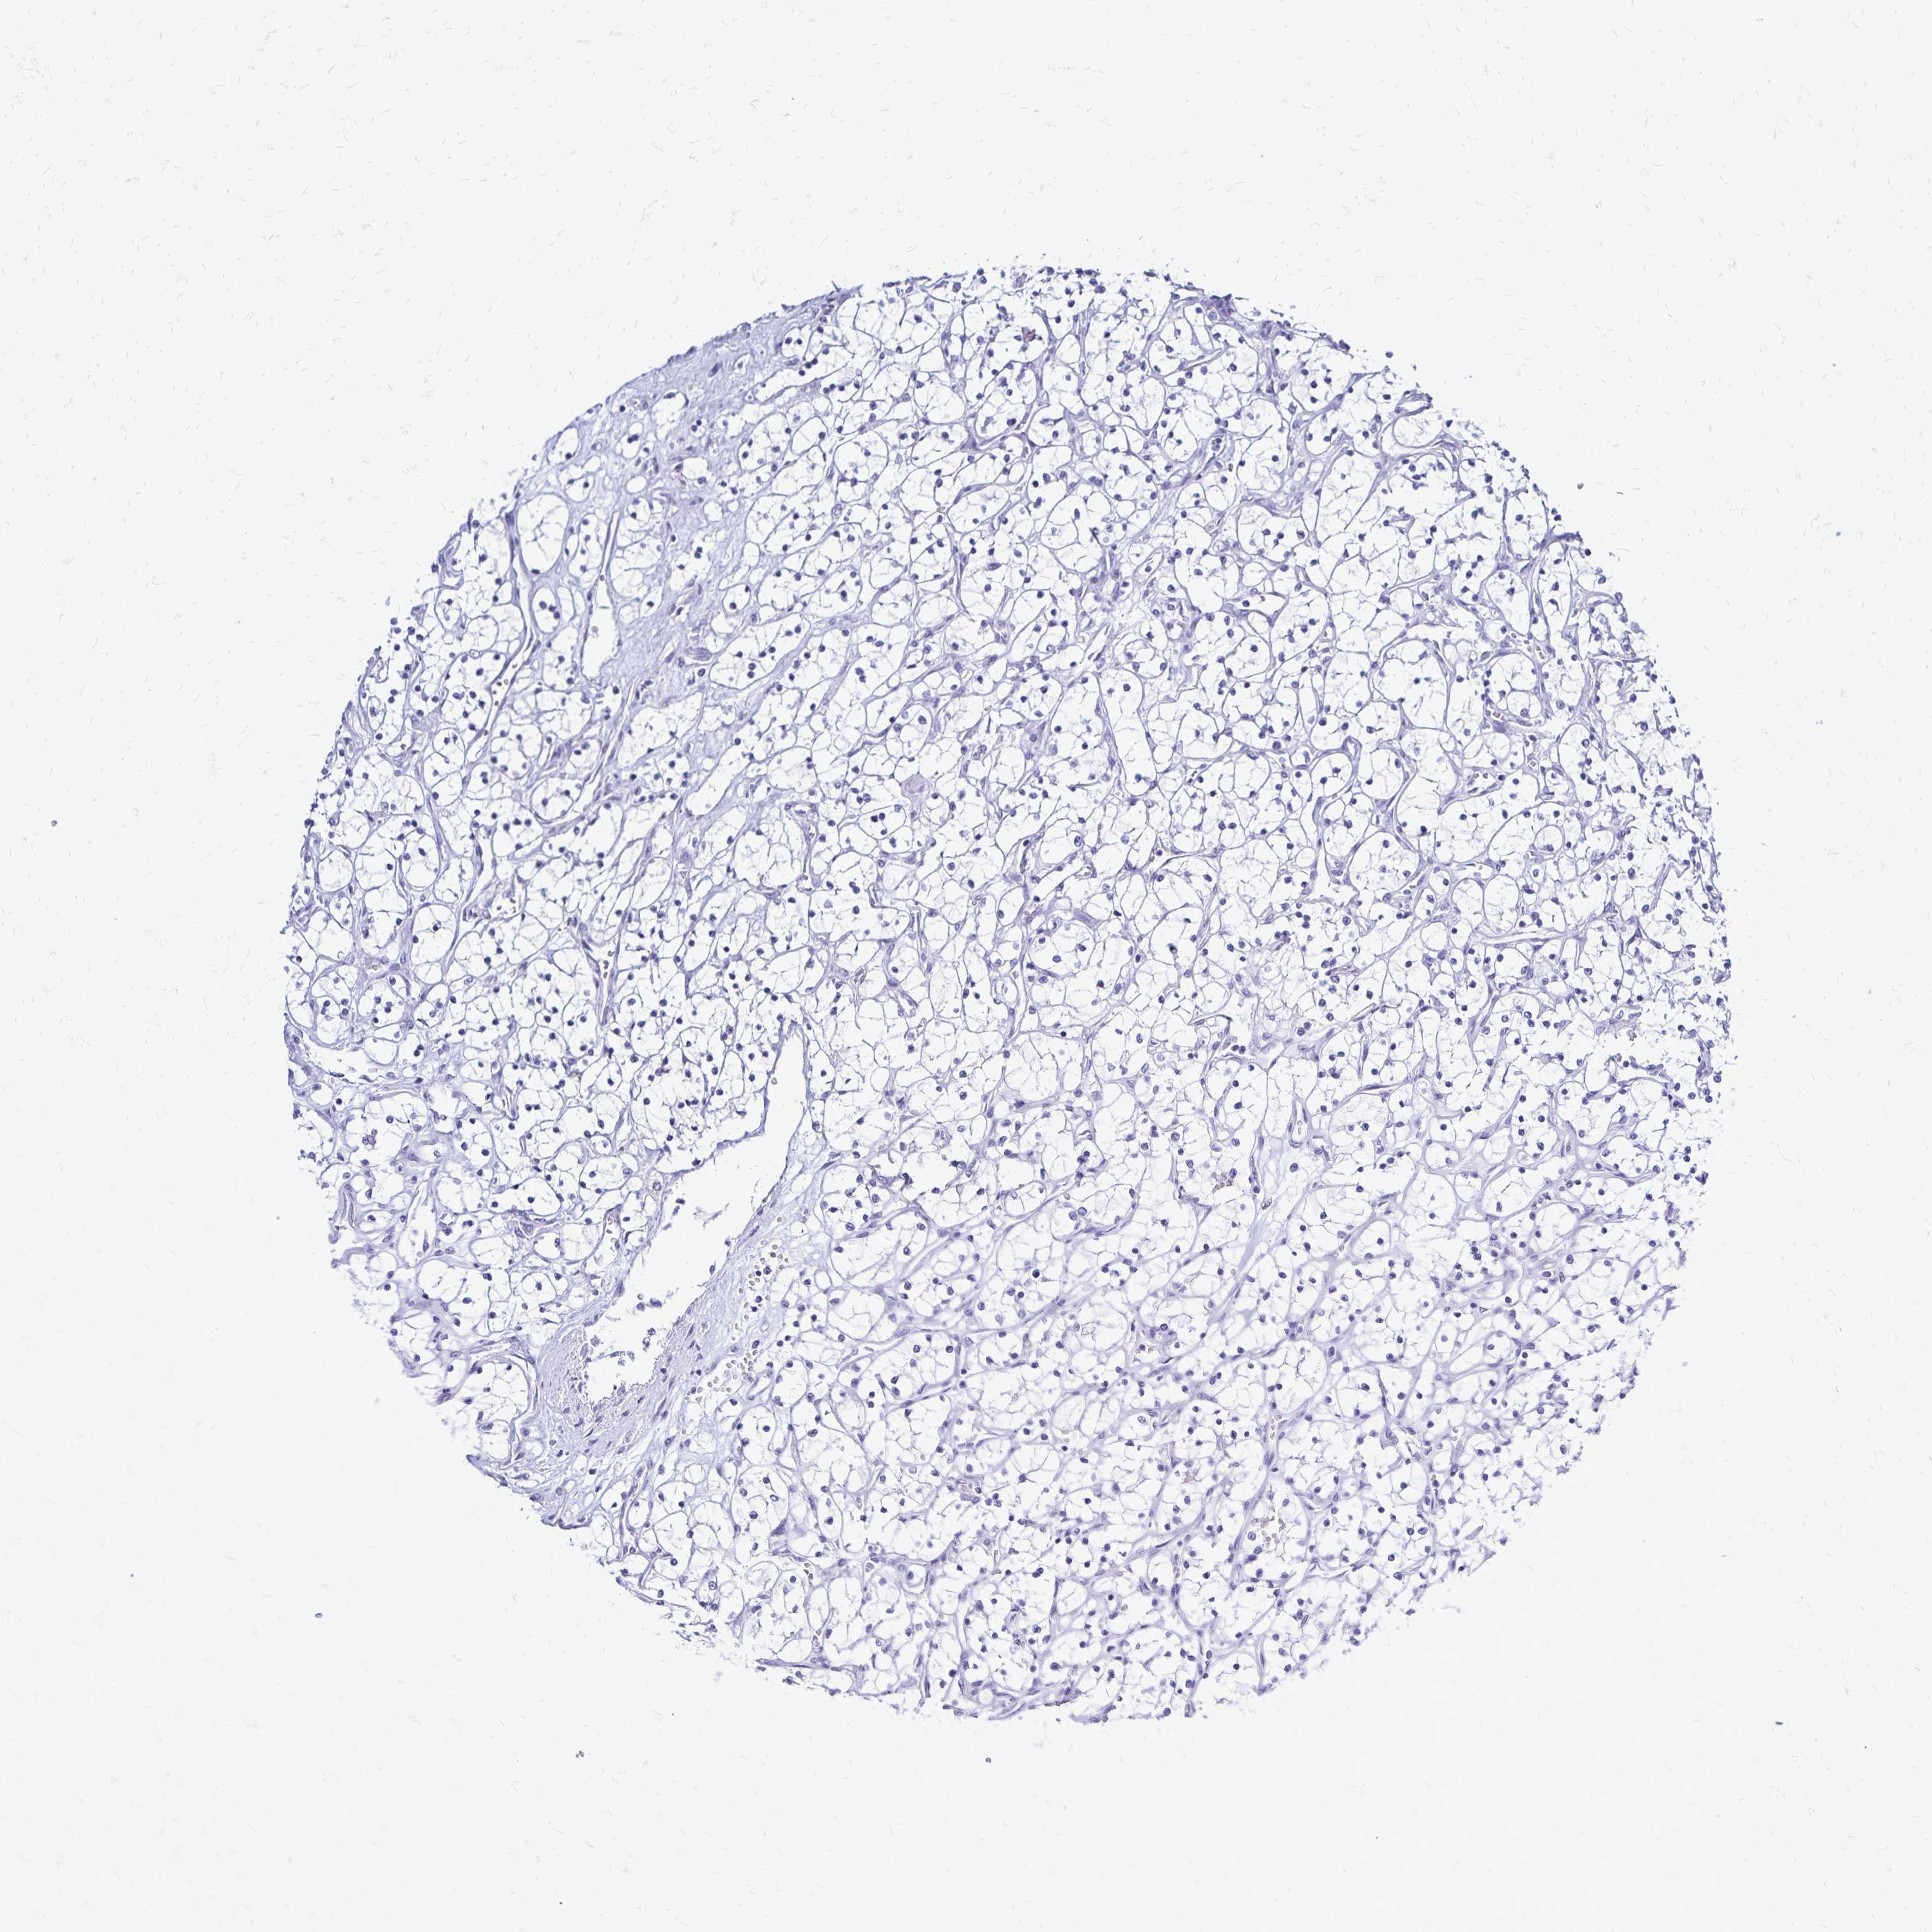

CANCER RENAL CANCER Show tissue menu

KICH TCGA KIRC TCGA KIRC VALIDATION KIRP TCGA PROTEIN RCC CPTAC PROTEIN EXPRESSION

Kidney chromophobe